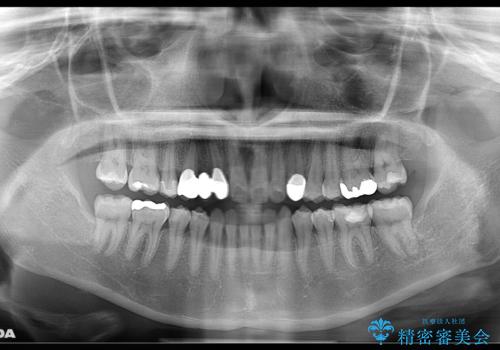

- 受け口で、前歯の嚙み合わせが気になるとの事でご相談にいらした方です。先天的に右上犬歯がなく、左上犬歯も小さい状態でした。矯正治療にて周囲の歯を動かして歯のスペースを確保した上で、被せものにて歯を作っていきました。